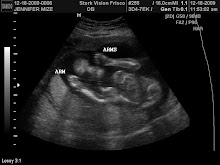

Baby Mize is 16 inches long and about 3 pounds now! He is really moving and shaking too! I wake up each morning and go to bed each night with him doing the hokey pokey! I feel great! My doctors appointments are every two weeks now so I am feeling really ready to have this sweet baby! Glucose and Iron testing last month went fine. His heartbeat is slowing down but as strong as it should be and he is quickly running out of room in my tummy. By the end of this pregnancy, he won't have a whole lot of room to spare! I am feeling so grateful that I feel so happy and healthy and am just so ready to meet him!